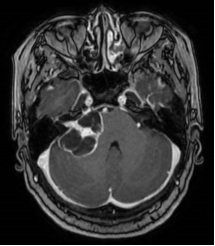

脑膜瘤术前核磁 术后CT